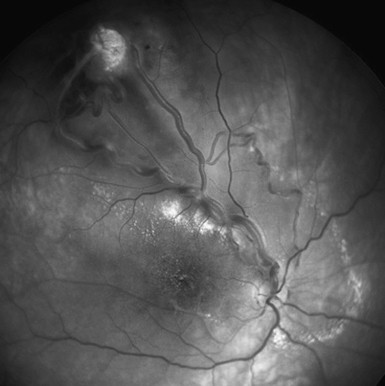

Congenital Vascular Malformations Of The Retina And Choroid Eye